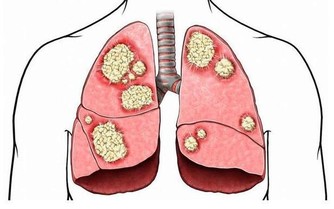

肺是人體極其重要的呼吸器官,是體內氧氣循環的關鍵。不過,現代很多人存在不良的生活和飲食習慣,比方說,時不時抽煙喝酒,動不動就熬夜……導致肺部功能或多或少受損,影響身體健康。那麼,肺好不好,可以通過哪些方法判斷?冬季養肺應該怎麼做?

肺好不好,不妨看看5個地方

如果在沒有感冒的情況下,睡覺前反复咳嗽,並且存在胸悶、胸痛的情況,就要考慮是否肺部出現問題,有可能是肺炎所致。

一般來說,如果人的肺部功能下降,那麼呼吸就會不規律,如變得急促或變得衰弱等,有時需要深呼吸才可以獲取足夠的氧氣。

所以,想知道自己的肺好不好,可以通過自身的呼吸情況判斷,具體將手指放在鼻孔下方,觀察呼吸是否均勻、正常即可。若是有呼吸困難、急促的現像出現,有可能是肺部出現病變,需要多加重視。